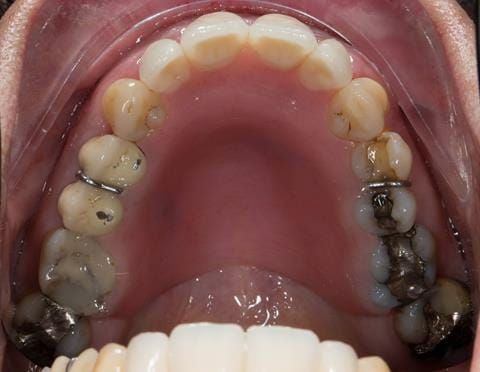

- UR2 peri-radicular periodontitis with a peri-radicular area on the root apex. Retrograde amalgam filling from a previous apicectomy. No visible root canal or root canal filling. Large circumferential marginal gap between the crown and tooth. Large post and core present. Very little tooth structure remaining resulting in a fragile tooth with increased potential for fracture.

- UR1 peri-radicular periodontitis with a small peri-radicular area on the root apex with wide blunderbuss apex. Radio-opaque root canal filling present approximately 3 mm short of the radiographic apex. Large circumferential marginal gap between the crown and tooth. Large post and core present. Very little tooth structure remaining resulting in a fragile tooth with increased potential for fracture.

- UL1 peri-radicular periodontitis with a peri-radicular area on the root apex. Retrograde amalgam filling from a previous apicectomy. Visible root canal space with no sign of root canal filling. Large circumferential marginal gap between the crown and tooth. Large post and core present. Very little tooth structure remaining resulting in a fragile tooth with increased potential for fracture.

- UL2 peri-radicular periodontitis with a peri-radicular area on the root apex. No visible root canal or root canal filling. Large circumferential marginal gap between the crown and tooth. Large post and core present. Very little tooth structure remaining resulting in a fragile tooth with increased potential for fracture.

- Other than the maxillary incisors the remaining dentition was in marginally better condition being moderately to heavily restored. Many will probably require replacement and restoration from time to time mainly from wear and tear owing to occlusal forces.